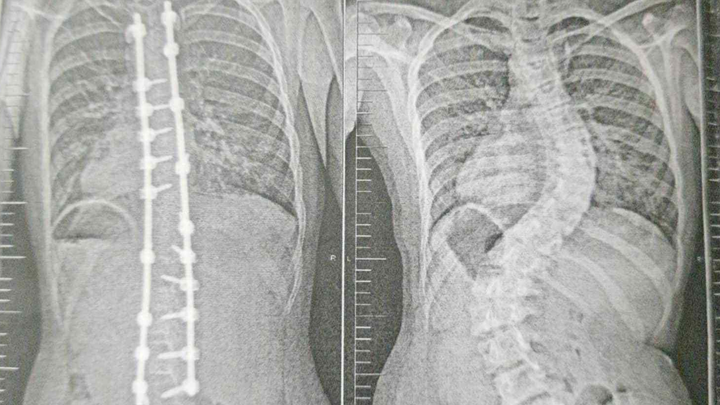

Under a year ago, my world was shaken when she was diagnosed with idiopathic adolescent scoliosis. Despite my hopes and efforts to slow its progression, her spine has curved to a devastating 60+ degrees, leaving her with only one option: life-changing surgery to protect her organs and her future.